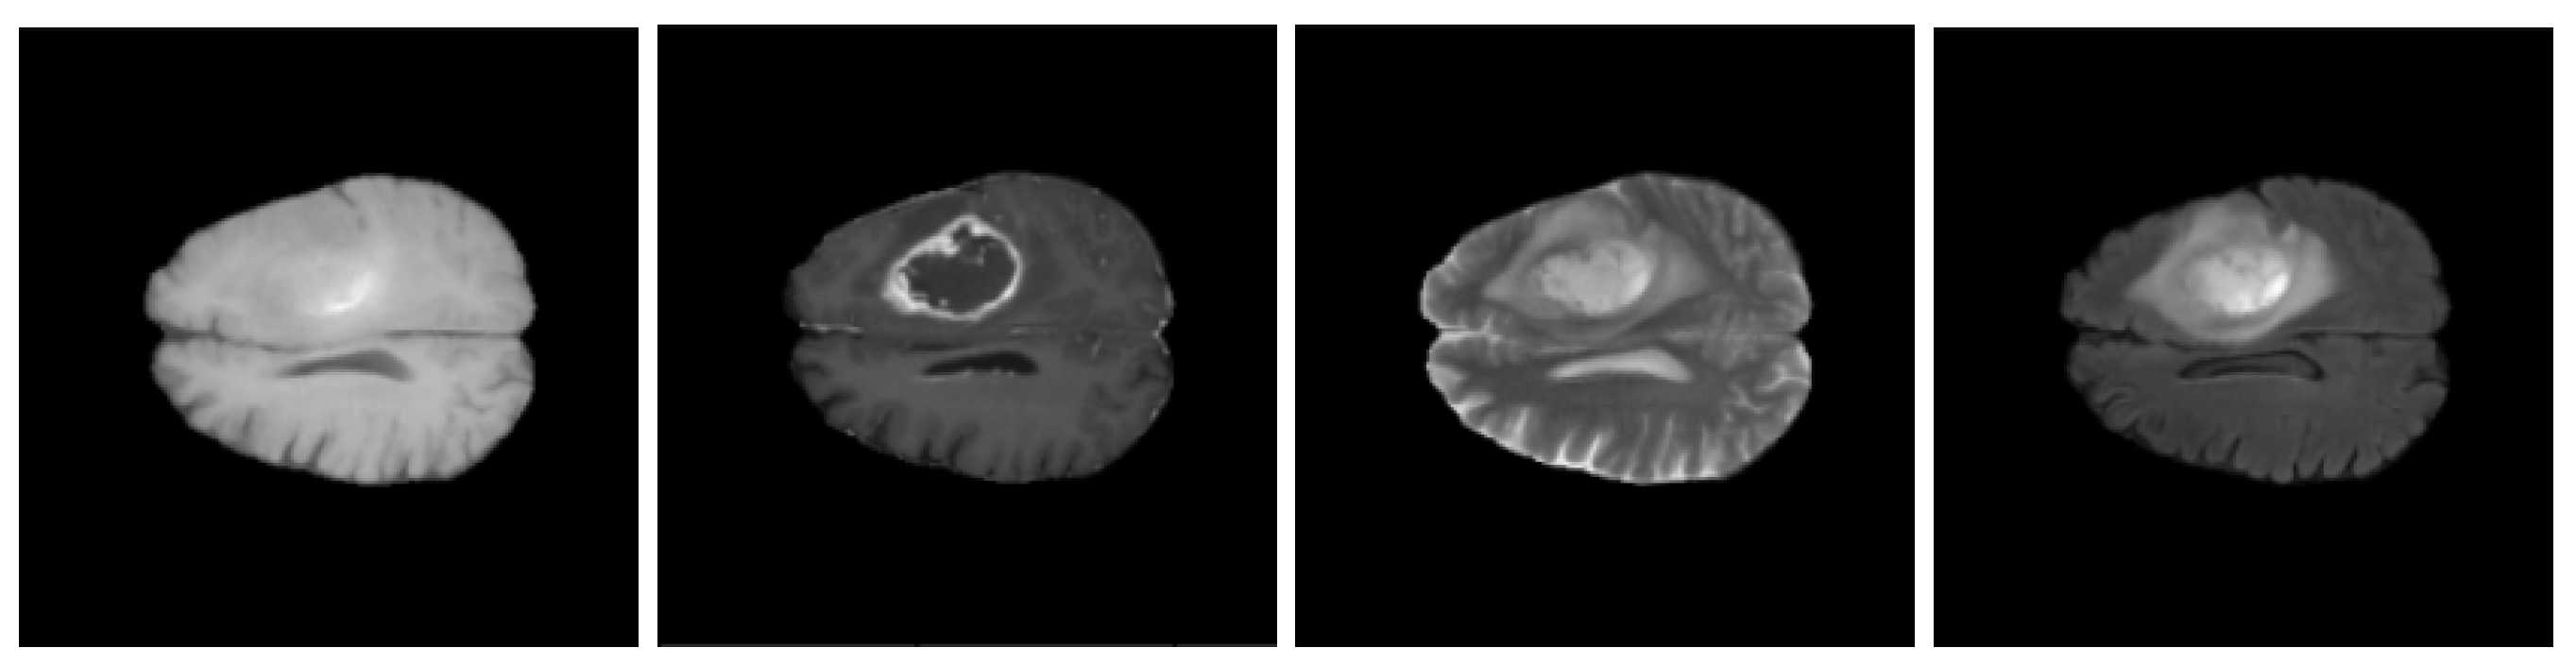

3.1. BraTS 2020 Dataset

3.2. Data Pre-Processing